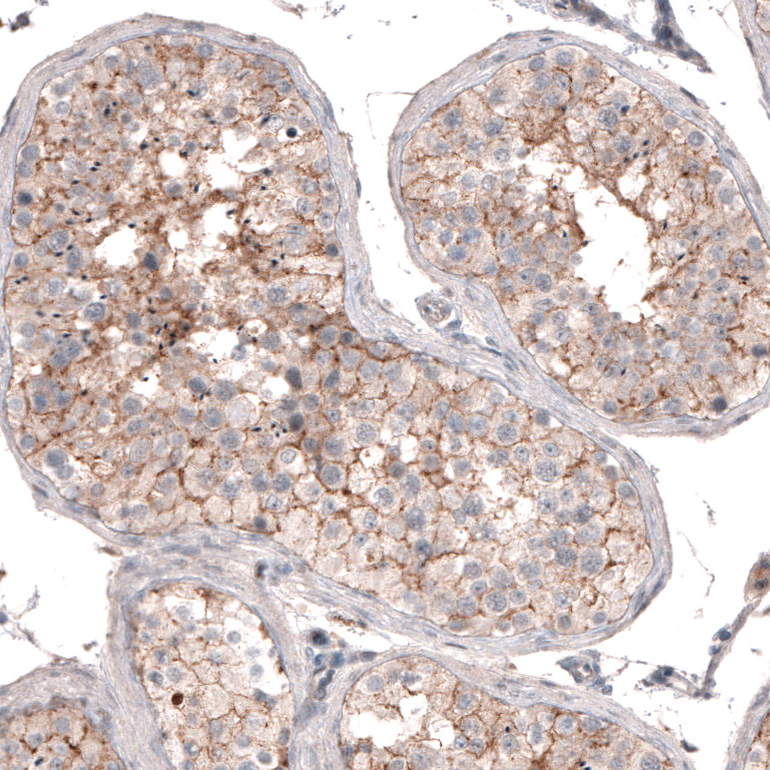

Immunohistochemical staining of human testis shows moderate membranous positivity in cells in seminiferous ducts.